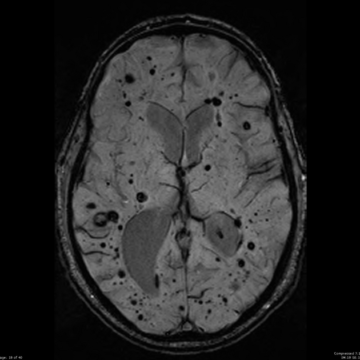

Imagem 1

Imagem 1:RM de encéfalo em sequência SWI/T2* mostrando múltiplas micro-hemorragias puntiformes lobares, predominantemente corticais e subcorticais, bilateralmente.Há poupança relativa de núcleos da base e tálamo, sem padrão profundo hipertensivo.Achados altamente sugestivos de angiopatia amiloide cerebral, com elevado risco de recorrência hemorrágica.